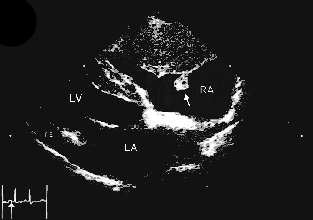

Hier einige Beispiele von Herzultraschall Untersuchungen:

Beispiel Herzultraschall idiopathischer Perikarderguss

Beispiel Herzultraschall eines Herzbasistumors

Beispiel Herzultraschall Hämangiosarkom

Ein Herzbeutelerguss kann nur sicher im Herzultraschall erkannt werden. Zusätzliche Hinweise liefern die klinische Untersuchung, das Röntgen sowie das EKG.